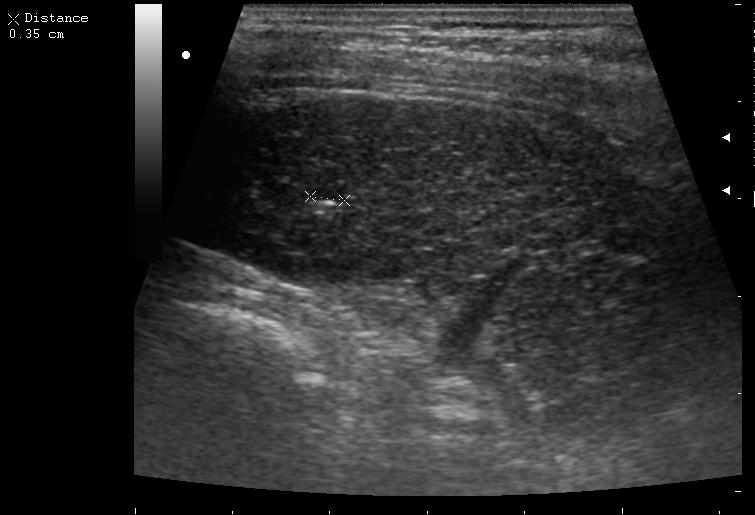

наезд большой черной Прады на маленькую (13кг) 5-летнюю девочку.

получает Медаксон, рабочая версия - изменение желчного пузыря вследствии травмы (шепотом - рекомендация хирургу сменить антибиотик)

и почему у меня нет датчика 14МГц....